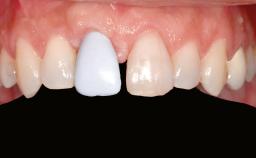

Iliac and Calvarial Bone Blocks for Onlay Grafting of a Severely Resorbed Edentulous Maxilla

A 45-year-old woman with a completely edentulous maxilla was referred to evaluate the possibility of rehabilitation with an implant-supported prosthesis. This patient was healthy and a non-smoker. She had been wearing a maxillary complete denture opposing a natural mandibular dentition since her twenties. This situation had resulted in progressive resorption of the alveolar ridge, repeatedly creating a need for relining the denture. Twenty years later, despite multiple adaptations and the use of “glues” the denture was unstable and causing the patient psychological and functional discomfort.